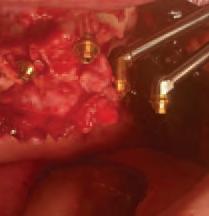

The zygomatic implant perforated (ZIP) flap for rehabilitation of patients with midfacial oncology defects: a report of three cases B. Martin, E. Cotter, C. Bowe, J.E. O’Connell

Issuu converts static files into: digital portfolios, online yearbooks, online catalogs, digital photo albums and more. Sign up and create your flipbook.